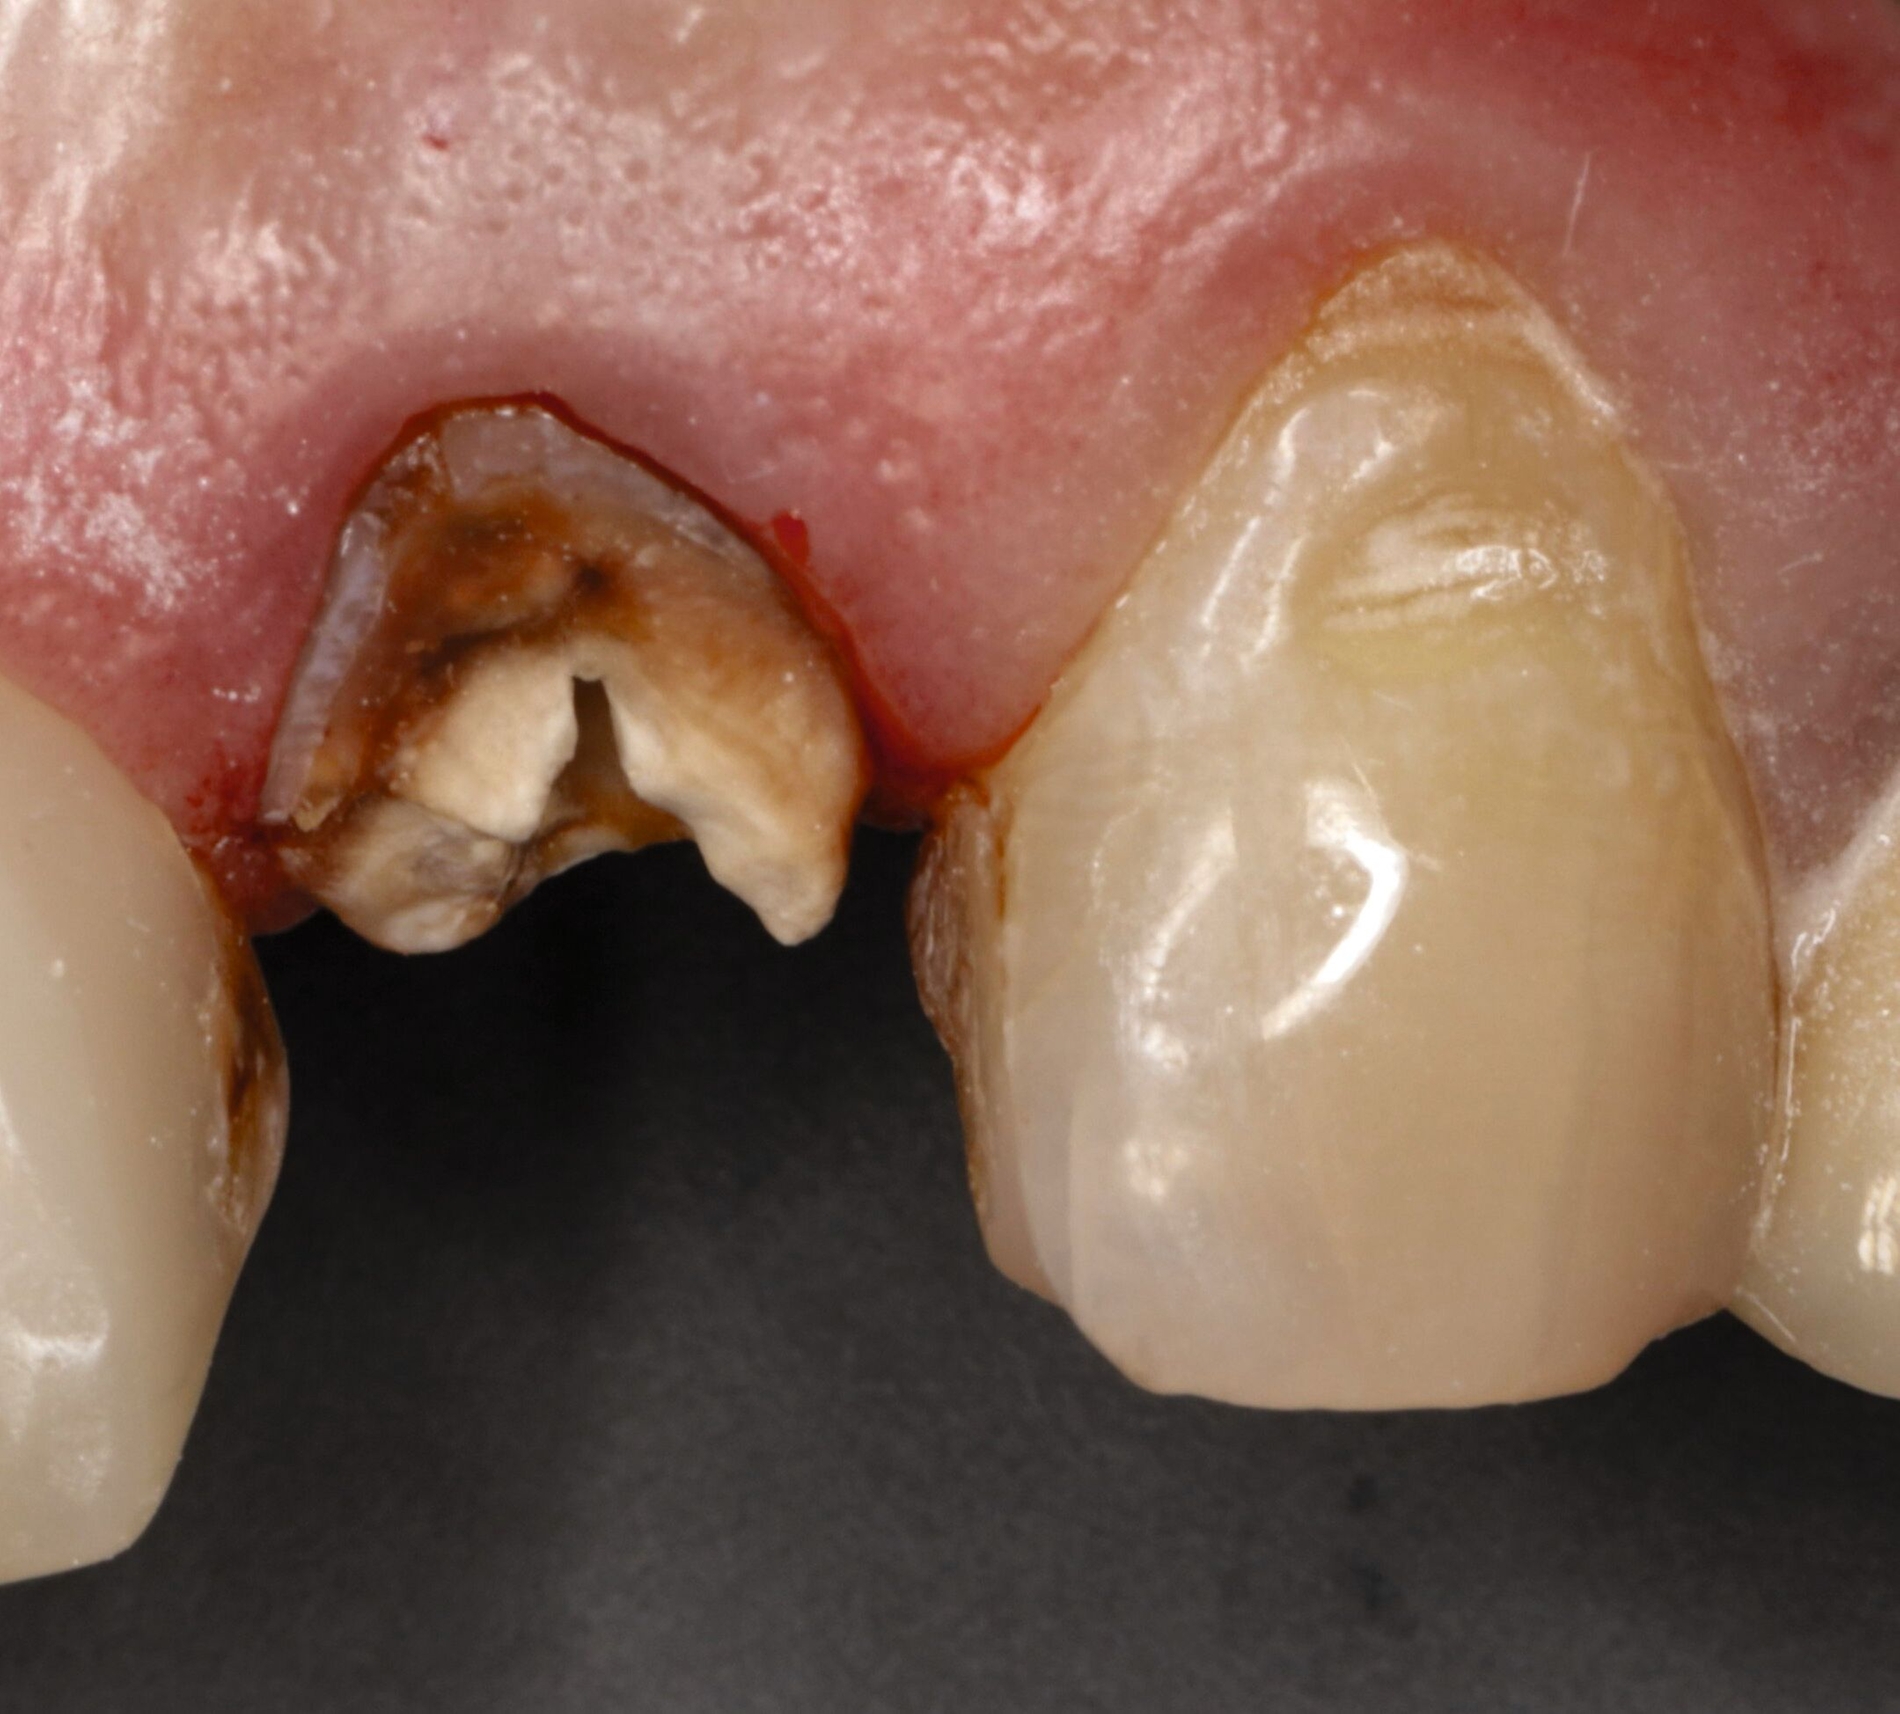

Vor 25 Jahren hatte der Patient ein Frontzahntrauma an Zahn 22 erlitten, der daraufhin mit einer Wurzelspitzenresektion und einer retrograden Amalgamfüllung versorgt worden war (Abbildung 3a). Dabei war die Zahnkrone mit einer keramisch verblendeten Stiftkrone aus Nichtedelmetall rekonstruiert worden, die nun aufgrund von Sekundärkaries insuffizient und gelockert war, jedoch keine Beschwerden verursachte. Klinisch wies der Zahn eine sehr kurze klinische Krone ohne ausreichendes Ferruledesign auf (Abbildung 5a) [Naumann et al., 2018a; Naumann et al., 2018b]. Neben dem Verdacht auf einen obliterierten mittleren Wurzelkanalabschnitt gab es röntgenologisch keinen Hinweis auf apikale Osteolysen oder parodontale Auffälligkeiten (Abbildung 3b). Der Patient entschied sich trotz des erhöhten Zahnhartsubstanzdefekts für den Zahnerhalt durch einen adhäsiv verankerten Kompositaufbau.

Für die restaurative Therapie von Zahn 22 wurde die alte Stiftkrone entfernt und die Stiftbohrung an die neue Indikation angepasst (Abbildungen 5a und 5b). Die Zahnkrone wurde dabei in drei Phasen wiederhergestellt: adhäsives Zementieren eines konfektionierten Glasfaserstifts, Stumpfaufbau und Modellation einer direkten Kompositkrone mit Silikonschlüssel, Frontzahnmatrize für komplexe Situationen und Schneepflugtechnik (Abbildungen 5c bis 5e) [Urkande et al., 2023; Amaro et al., 2021; Frese, 2020; Mannocci et al., 2002; Dimitrouli et al., 2011; Opdam et al., 2003]. Im Röntgenkontrollbild zeigt sich ein suffizienter Stiftaufbau (Abbildung 6).